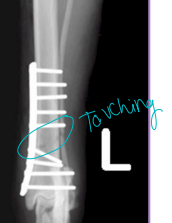

Complications of Bone Healing

Dt: Take xrays every 4-6 weeks postop** compare pre/post op

Malunion: Fracture healed in abnormal alignment

Varus: distal limb deviates medially: elbow/knee away

Valgus: distal limb deviates laterally: elbow/knees touching

Torsion: bone rotated on long axis

Translation: displacement, longitudinal axis intact

Recurvatum: apex caudal, distal limb cranial to fracture

Procurvatum (antecurvatum): apex cranial, distal limb caudal to fracture